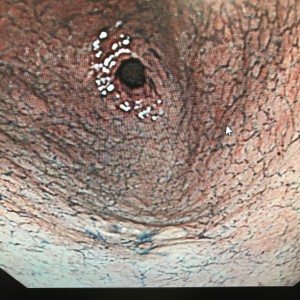

前庭部大弯の20mm弱の白色調0-Ⅱa病変でESDを施行した症例です。

術前診断としては病変は柔らかく,酢酸撒布をしても表面構造がしっかりと確認でき,分化型早期胃癌(深達度M)の診断でESD導入となりました。